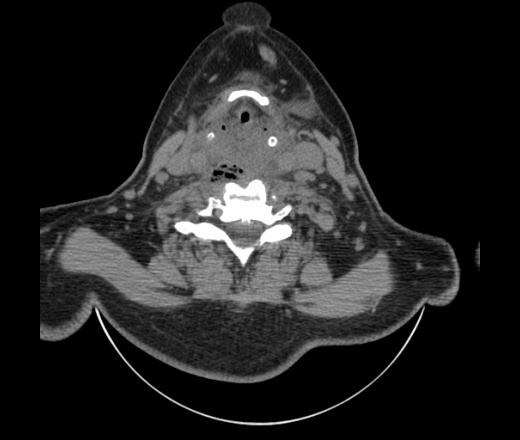

Женщина поступила в х/о спустя 4 дня после того как при употреблении карася подавилась костью.

Наличие газа в средостении на протяжении тел С2-С6 (медиастинальна эмфизема); рыбная кость на уровне тела С6.

При всем уважении, но говорить о медиастинальной эмфиземе, оценивая мягкие ткани шеи, как-то слишком резко. На мой взгляд, это ретрофарингеальное пространство.

Эвакуировали почти 100мл гноя. Но кость не смогли найти. Думаю что она даст дальнейшее ослоднение. Эндоскопически за черпалонадгортаной звязкой не смогли зайти в пищевод, все мягкие ткани отечные, просвет пищевода сдавлен. По всей видимости параэзофагеальная клетчака тоже задействована. Эмпиема, если ее можно так назвать, незнаю как правильно дошла до уровня яремной вырезки. Чем закончиться напишу. Ждем медиастинита.

Согласен с Вами; конечно, наличие газа в клетчатке ретрофарингеального пространства (затмение с опечаткой..). К сожалению, процесс "продвигается" к медиастиниту. Но почему никто, не отмечает наличие рыб. кости; или это для Всех очевидно?

Кость то мы сразу выявили, размеры где то 17*2мм, но ее так и не получается найти в этой каше